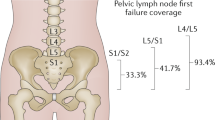

Clinical endpoints

Clinical endpoints considered were acute and sub-acute GU adverse events graded per CTCAE v5.0 and total International Prostate Symptom Score48,49 (IPSS). Acute GU toxicities were defined as toxicities that occurred before the end of RT and sub-acute GU toxicities were toxicities that occurred after RT. GU toxicities considered were frequency, nocturia, dysuria, urgency, urinary obstructive symptoms, and incontinence. A summary of the percentages of events for the outcomes and BED levels is shown in Supplementary Table S2. A visual representation of the categorization of the clinical endpoints is shown in Fig. 2.